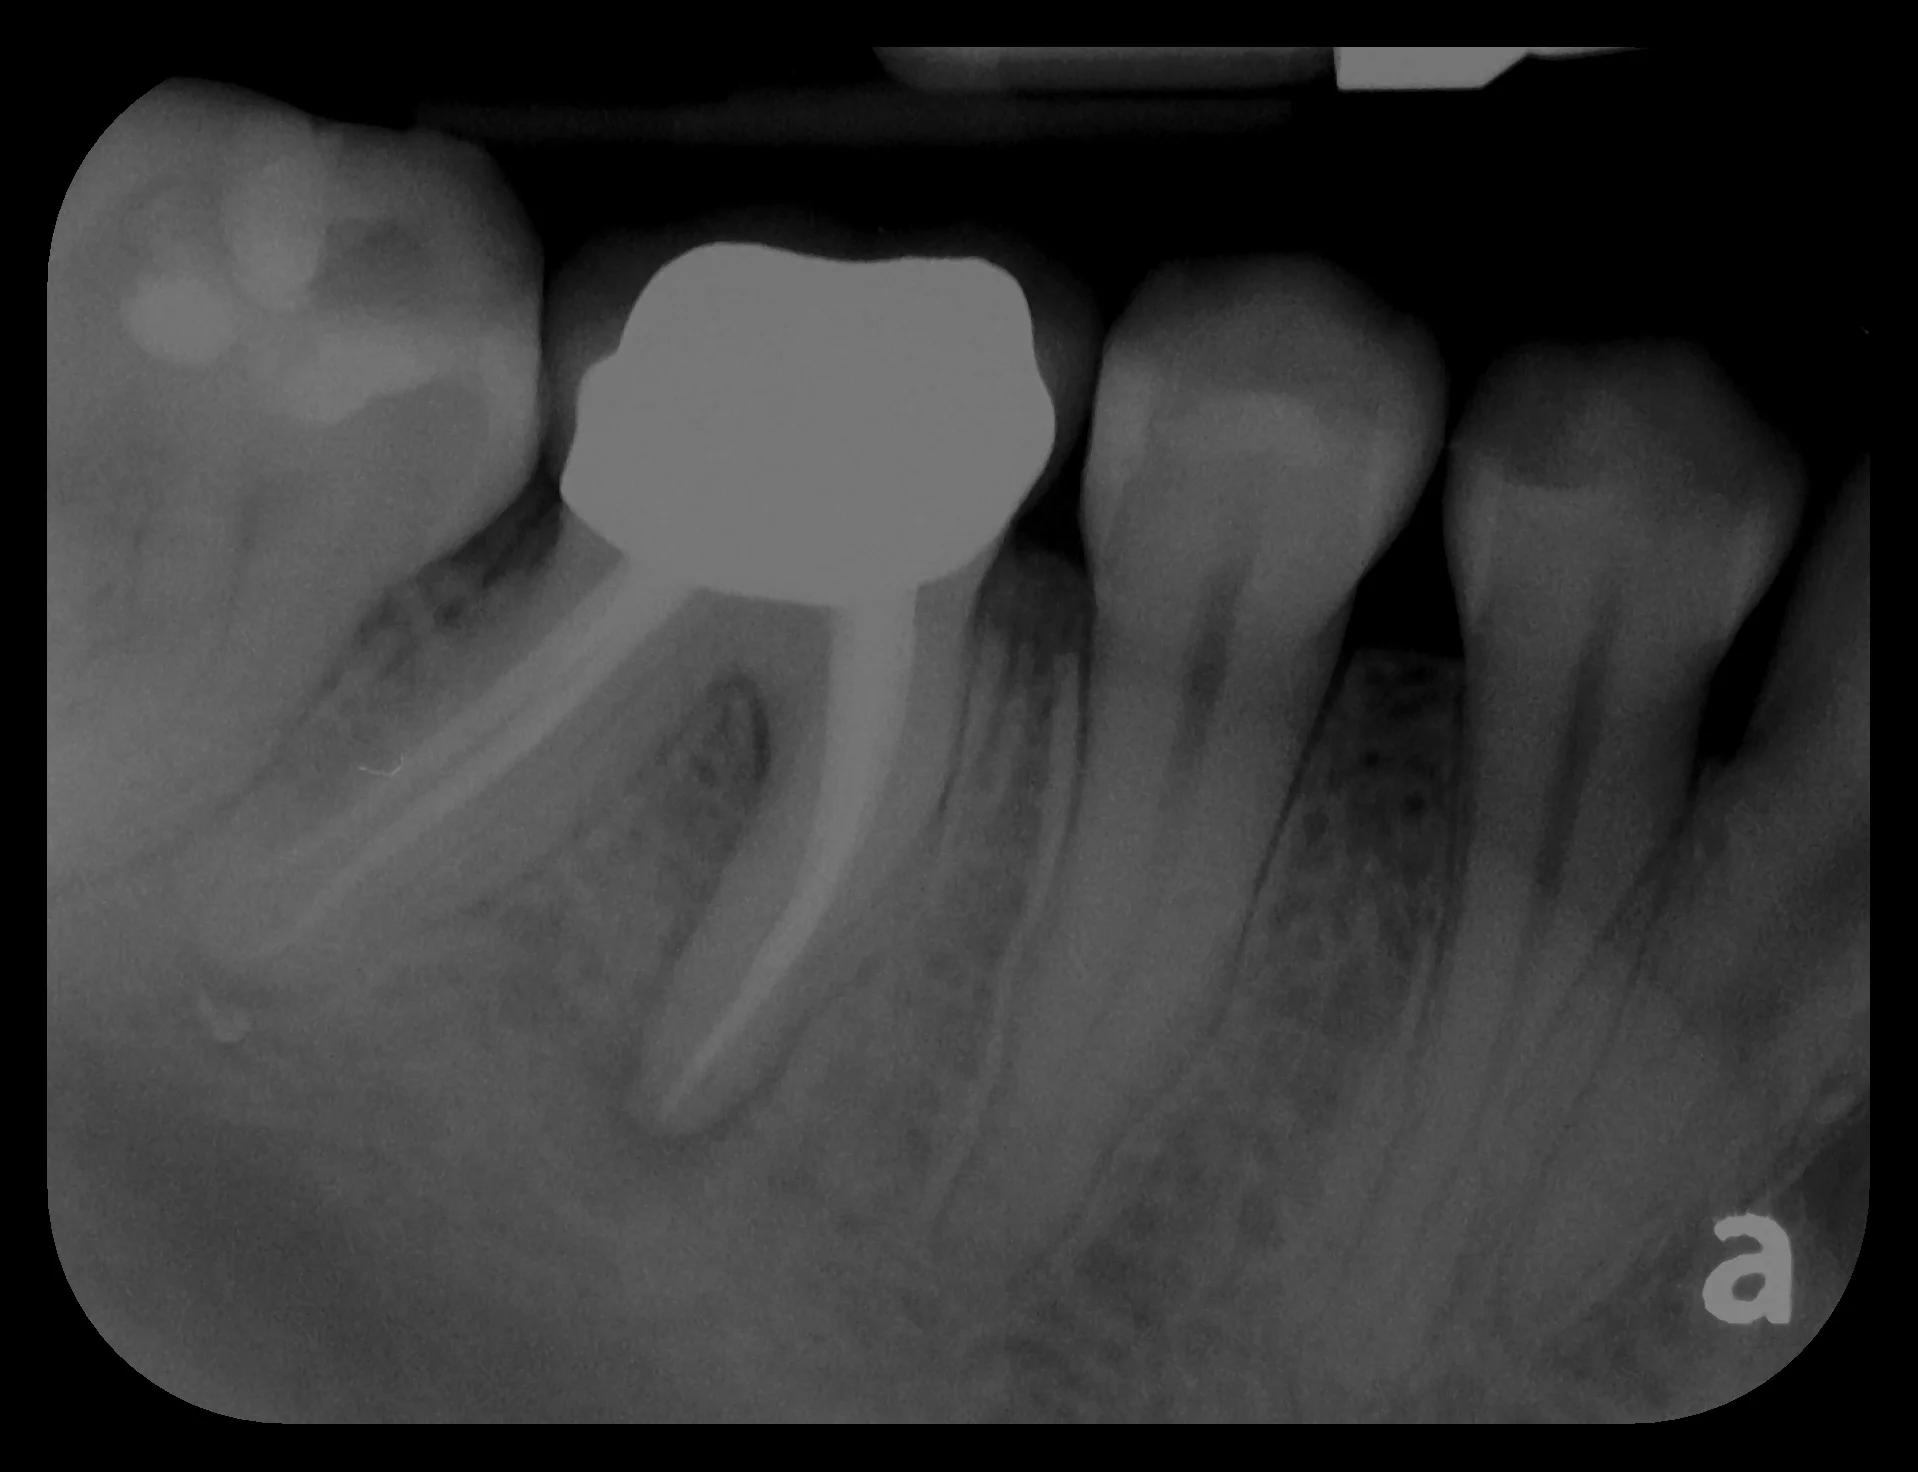

Our patient presented with a crown that popped off. After a thorough exam, our team observed that this tooth had a long history of dental treatments.  A previous doctor performed a root canal, then placed a metal screw inside of the root to hold a metal crown.  Over the years, the tooth became soft from cavities and infected but the patient did not know this was happening because once a root canal is performed, the tooth has no feeling!  Then one day, the crown popped off and she came to our office.  Unfortunately we could not save the tooth and an implant was the best option.  We decided to extract the tooth and perform a bone graft since some of her bone melted away due to tooth infection.  After the bone graft healed, we placed a Nobel Biocare implant then connected her brand new BruxZir porcelain crown to a custom gold abutment!  Our patient is happy and chewing confidently again!